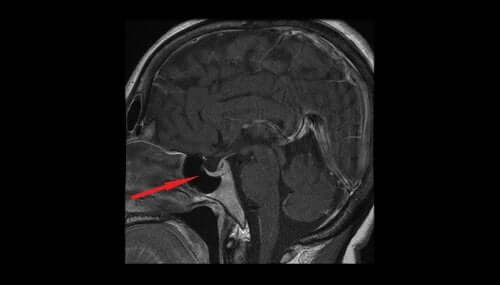

Cele mai relevante teste pentru confirmarea diagnosticului sunt cele care vizează câmpul vizual și creierul (metode de investigație imagistice precum rezonanța magnetică nucleară sau computerul tomograf).

- Intervențiile chirurgicale: În mod obișnuit, adenoamele hipofizare se extirpă prin intermediul cavității nazale. Uneori însă, este nevoie de craniotomie sau de deschiderea craniului.

- Intervenția endoscopică nazală: Constă în introducerea unui endoscop într-una din nări și împingerea acestuia între turbina mijlocie și septul nazal, până când este localizată gaura rotundă a sfenoidului. Acest orificiu poate fi mărit, astfel încât sinusul sfenoid să devină suficient de deschis pentru ca podeaua șeii turcești să fie vizibilă și să se îndepărteze tumoarea.